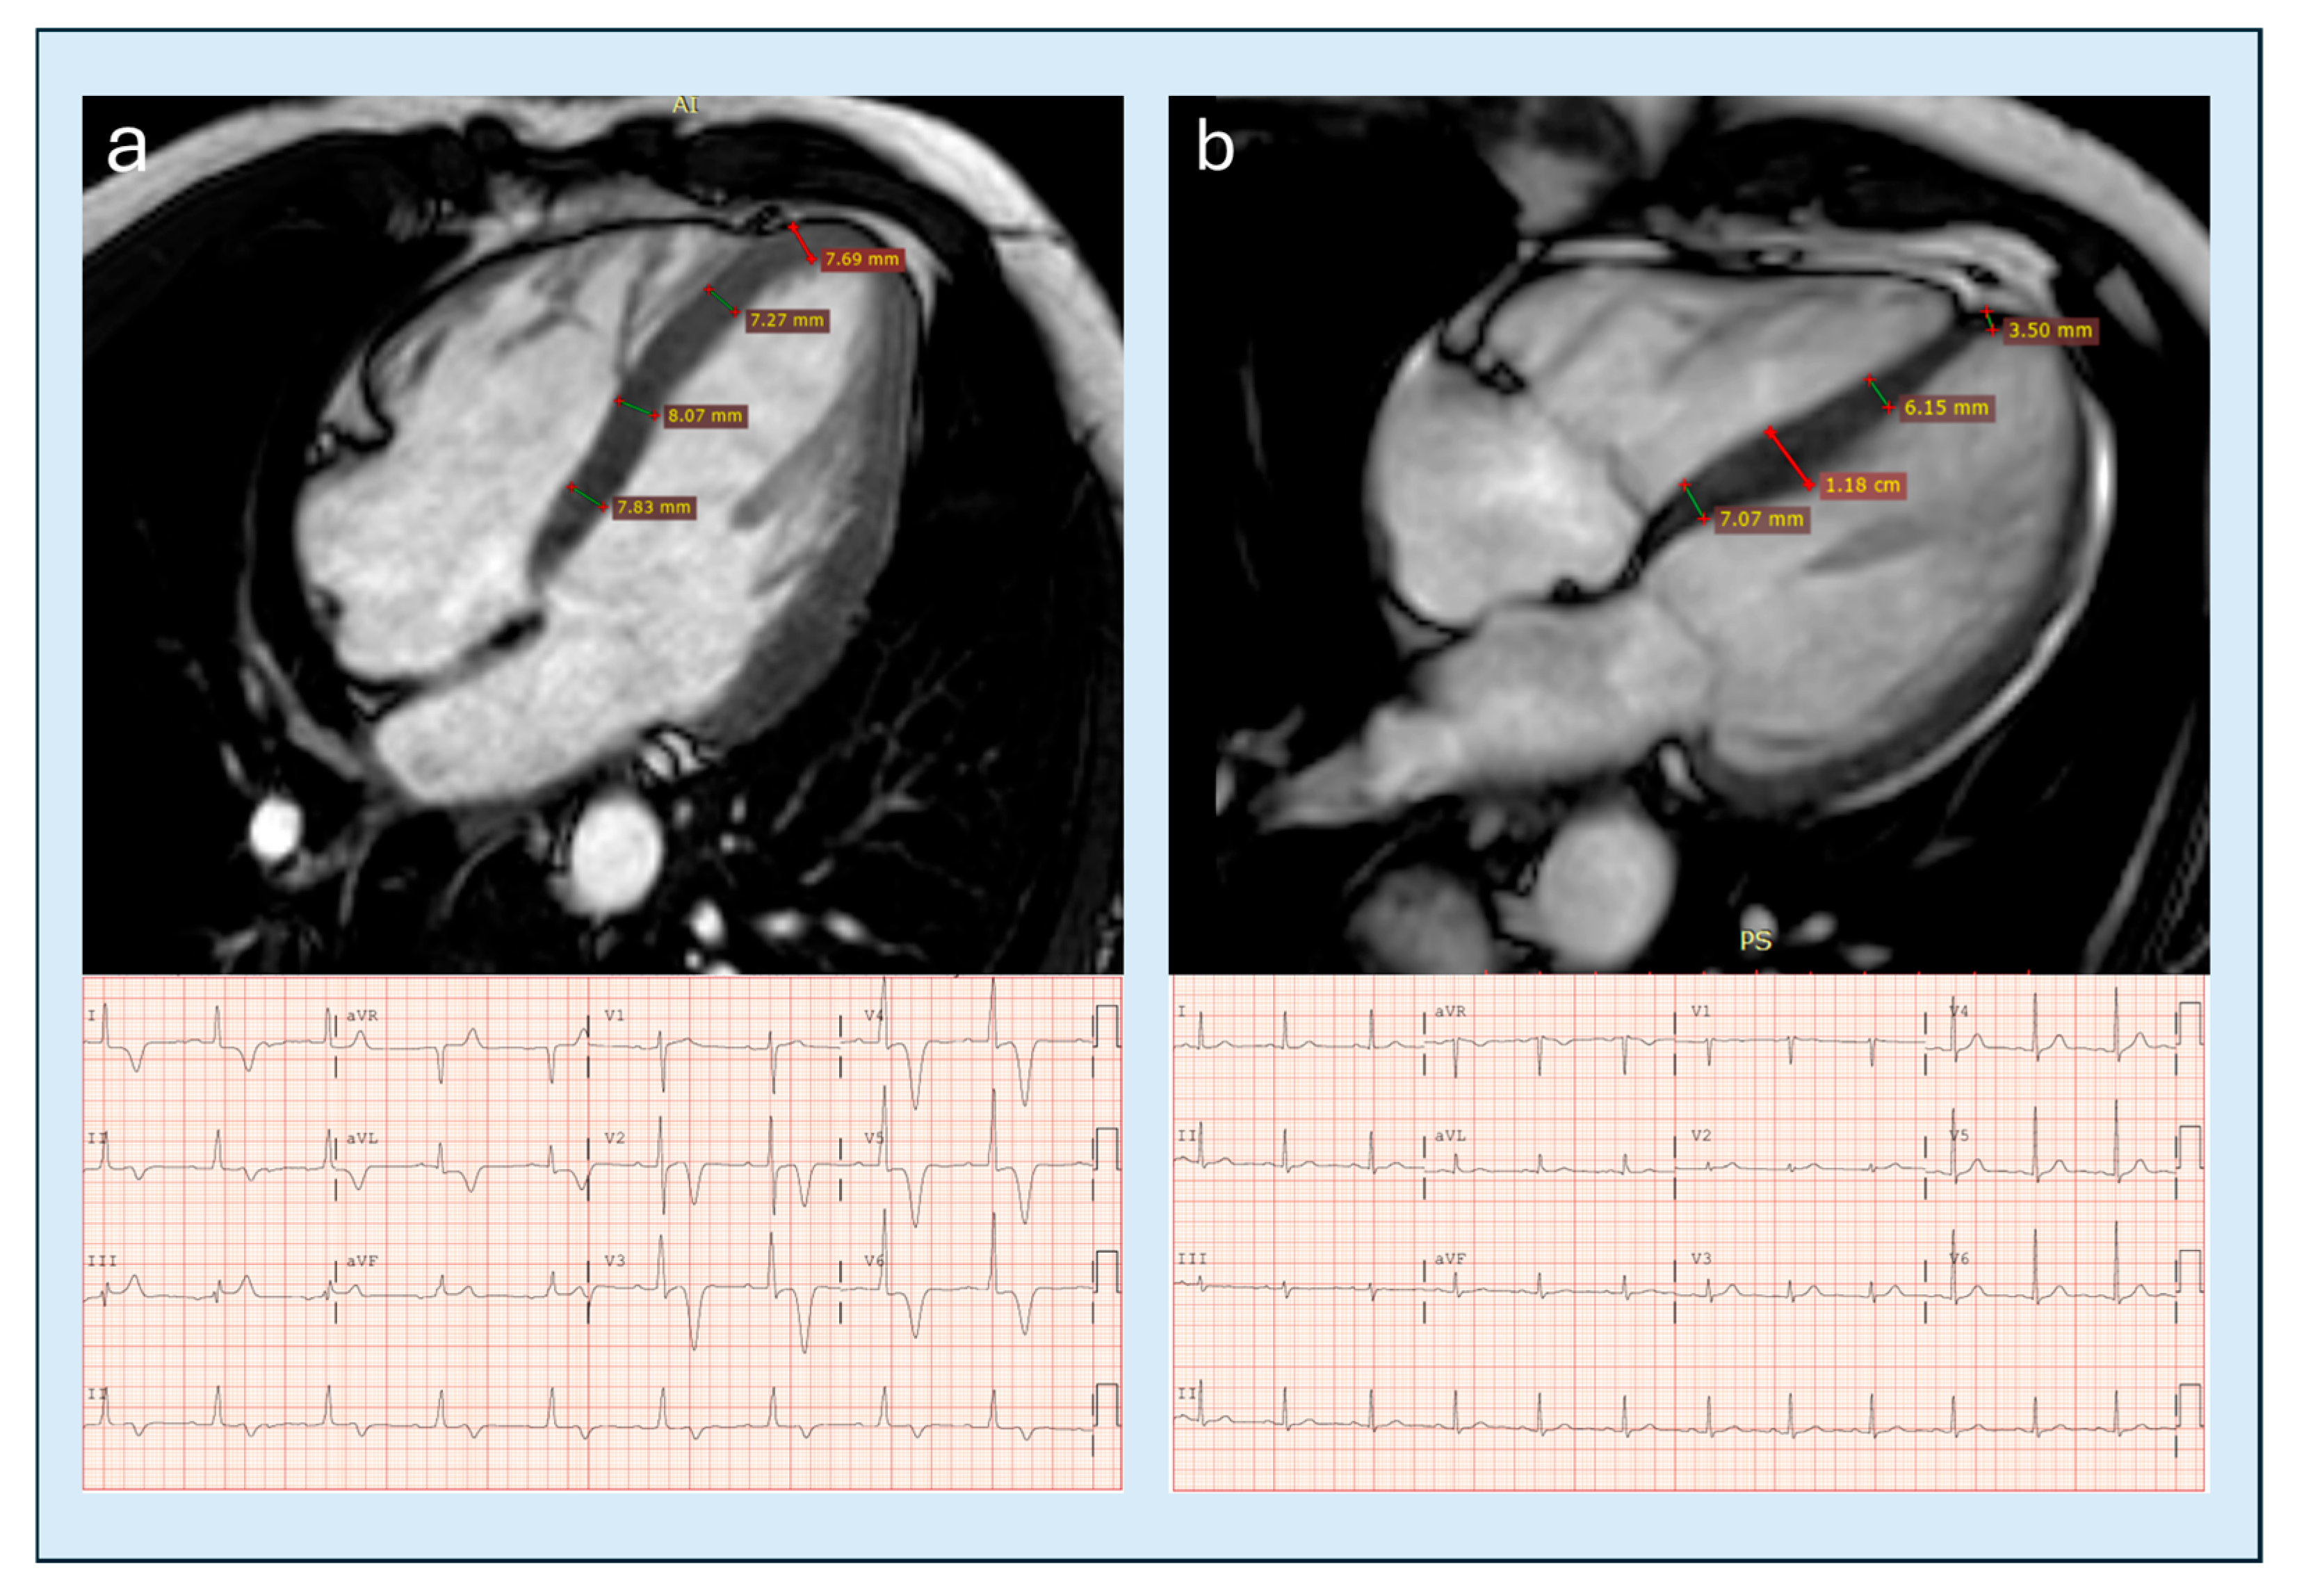

6.1. Cine-MR and Morphology

- Hughes, R.K.; Shiwani, H.; Rosmini, S.; Augusto, J.B.; Burke, L.; Jiang, Y.; Pierce, I.; Joy, G.; Castelletti, S.; Orini, M.; et al. Improved Diagnostic Criteria for Apical Hypertrophic Cardiomyopathy. JACC Cardiovasc. Imaging 2024, 17, 501–512. [Google Scholar] [CrossRef] [PubMed]

- Flett, A.S.; Maestrini, V.; Milliken, D.; Fontana, M.; Treibel, T.A.; Harb, R. Diagnosis of apical hypertrophic cardiomyopathy: T-wave inversion and relative but not absolute apical left ventricular hypertrophy. Int. J. Cardiol. 2015, 183, 143–148. [Google Scholar] [CrossRef]

| Indexed apical maximum wall thickness | CMRi | ≥5.2–5.6 mm/m2 | >4000 controls +104 ApHCM pts | AUC 0.94; Sens 99/78%; FP 3% | High | ++ | Hughes 2024 [25] |

| Loss of basal–apical tapering | CMRi | Apical ≥ basal | 22 relative ApHCM vs. controls | Supportive; no AUC | Moderate | +++ | Flett 2015 [74] |

| Apical–basal thickness ratio | CMRi | >1 (prev ≥1.3) | Mixed CMR cohorts | Not available | Moderate | +++ | Flett 2015 [74] |

| Apical angle | CMRi | ≤75–76° | 71 pts | AUC 0.77 | Low–mod | ++ | Li 2021 [64] |

| Apical thickness progression | CMRi | Mean ≥7.6 mm; Max ≥9.5 mm | 71 pts | AUC 0.87–0.898 | Moderate | ++ | Li 2021 [64] |